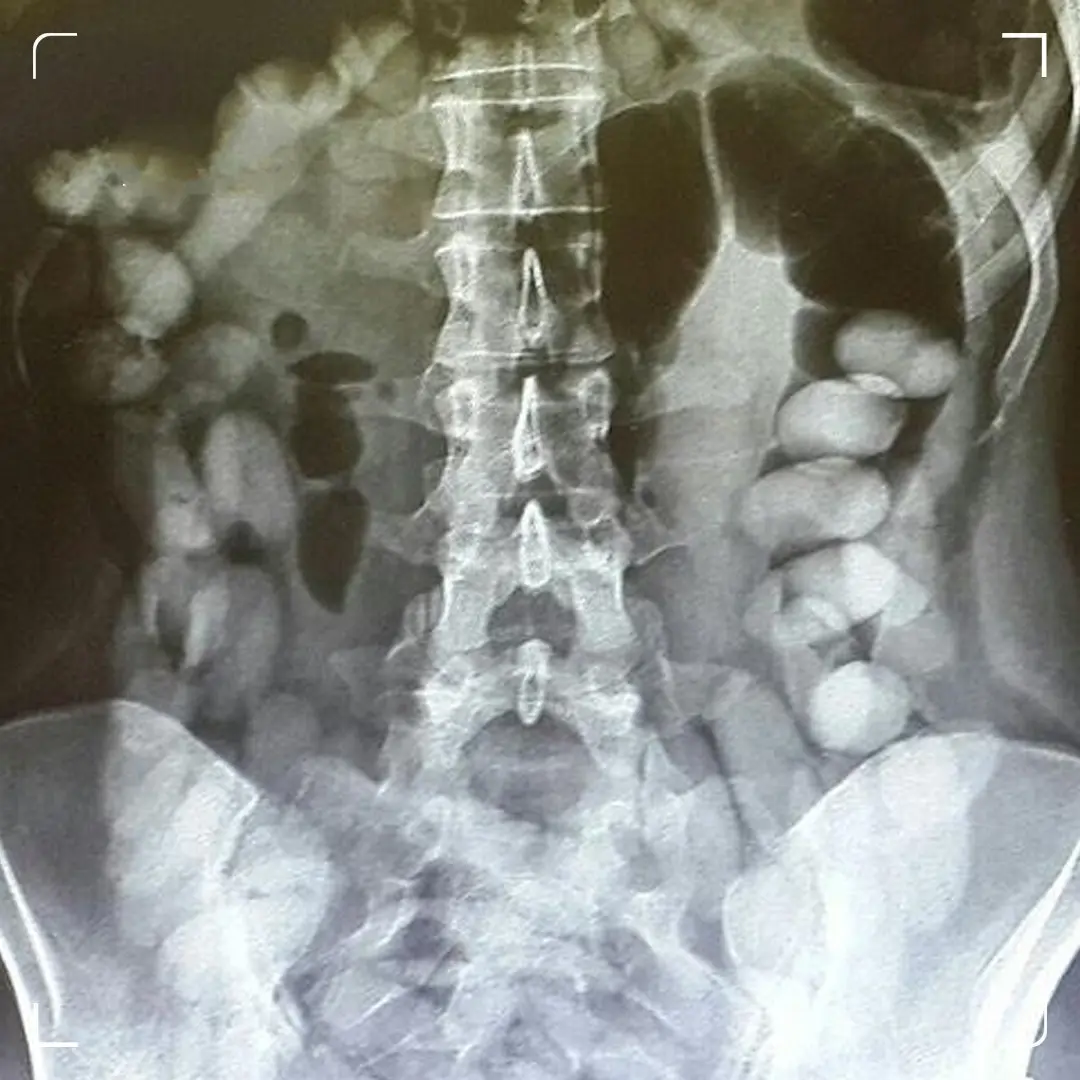

به گزارش سایت دیده‌بان ایران؛ کاشانی رئیس بیمارستان شهید محمدی بندرعباس با اعلام خبر خروج بیش از ۱۰۰ بسته مواد مخدر جاسازی شده از بدن یک جوان ۲۲ ساله اظهار کرد: این جوان در تاریخ ۱۴۰۳/۱۰/۷ در شهر حاجی آباد تصادف کرده و به مرکز درمانی حاجی آباد منتقل شد که به دنبال بررسی‌های مختلف درمانی مشخص می‌شود که فرد حامل پک‌های مواد مخدر در شکمش بوده است.

وی افزود: بیمار به دلیل کاهش سطح هوشیاری و نیاز به جراح مغز و اعصاب سریعاً به مجتمع آموزشی درمانی پیامبر اعظم (ص) منتقل می‌شود و سریعاً سی تی اسکن شده و به اتاق عمل جهت جراحی انتقال می‌یابد.

روانبخش مدیر تیم اتاق عمل نیز در این رابطه گفت: تیم اتاق عمل در طول شب در حال جراحی و خارج کردن پک‌های مواد مخدر بودند که تعدادی بالغ بر ۱۰۰ پک به وزن کلی بیش از یک کیلوگرم از بدن بیمار خارج شد که تحویل مقام حراست بیمارستان و مقامات انتظامی داده شد.